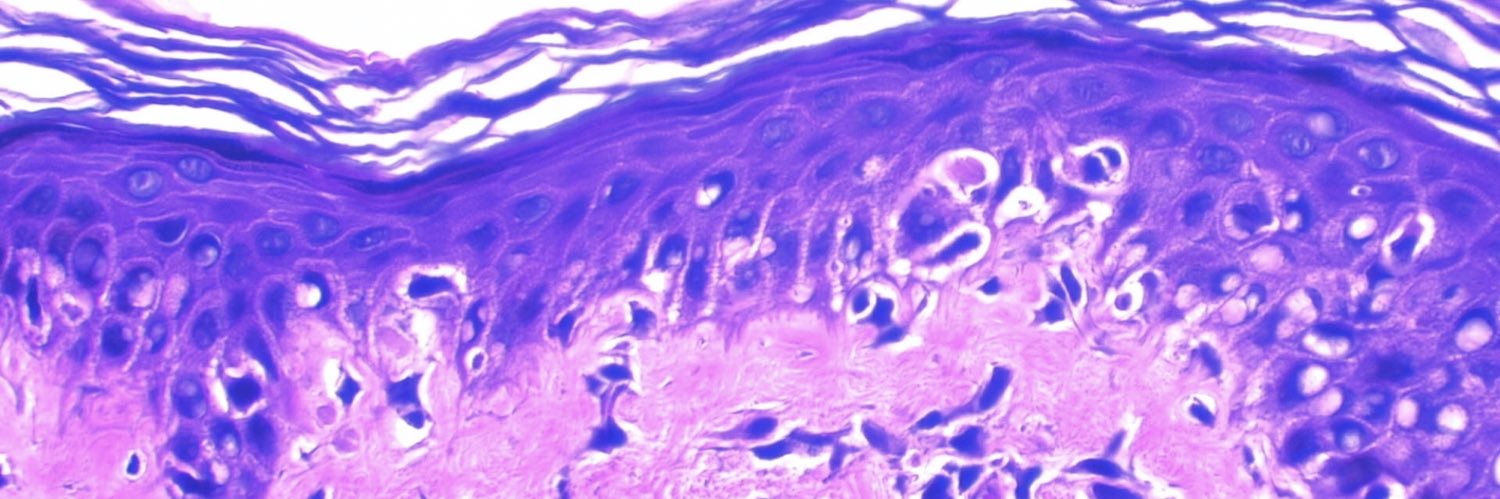

MD, PhD, Pathologist. Instituto de Patologia de Araçatuba-SP , faculdade de medicina Unisalesiano Araçatuba-SP / Brasil / @karger science Ambassador